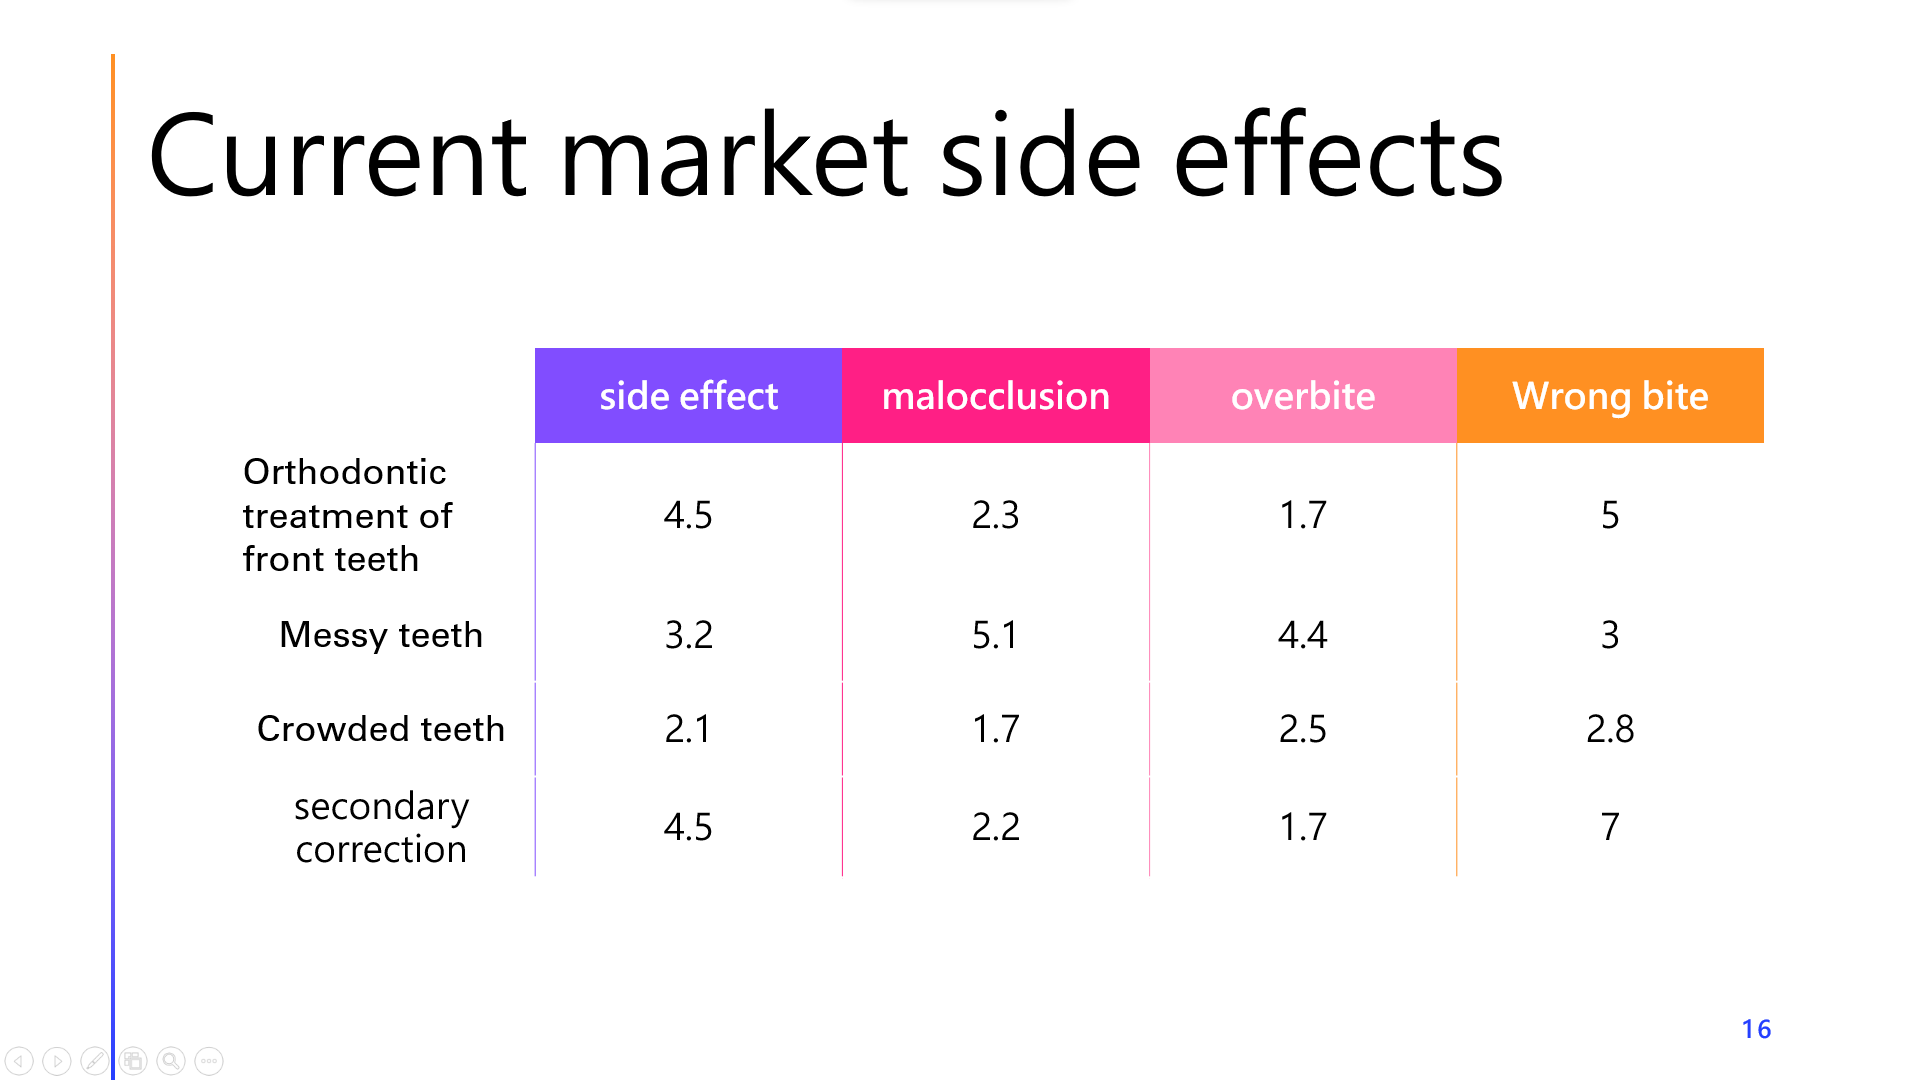

Invisalign invisible correction case

- Slight dental asymmetry - front teeth correction

- Mild dental asymmetry/front teeth correction

- The teeth of college students are not very messy, with only the upper front teeth slightly asymmetrical, and no obvious messy or bite problems. It took less than a year to successfully complete the correction of the front teeth.

- Slightly messy teeth - gaps between teeth - crowded teeth

- The upper teeth are slightly messy and have small gaps, and the lower teeth are crowded, making cleaning difficult and the gums swollen. The gap between the upper front teeth was closed and the lower front teeth were aligned, and the correction was successfully completed within nine months.

- Secondary correction - gap between front teeth - crowded teethSecondary correction / gap between front teeth / crowded teeth

- I had undergone orthodontic treatment, but after the correction I still had problems such as a large gap between my front teeth and slight tooth crowding. The doctor used Invisalign for his secondary correction, using invisible braces to close the gap between his upper front teeth and straighten his lower front teeth for slight correction.